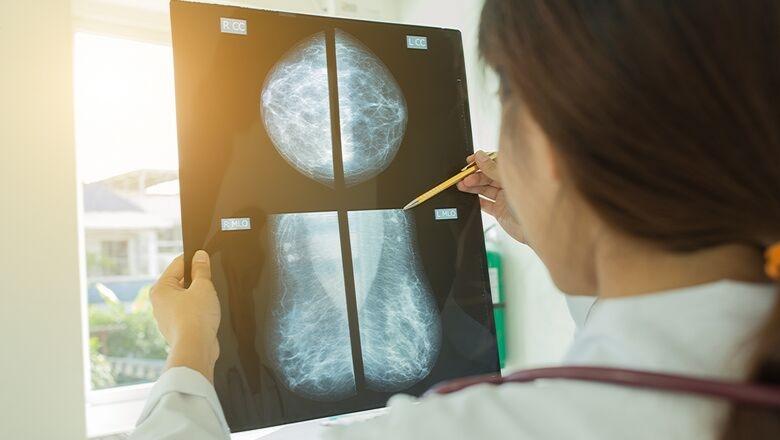

Breast Cancer Now has claimed that nearly 11,000 people in the UK could be living with breast cancer that has not yet been diagnosed due to disruption caused by the coronavirus pandemic.

The charity estimates that around 10,700 fewer people across the UK were diagnosed with breast cancer between March and December 2020 as a direct result of the impacts of the pandemic and warns that in the worst cases some women could die as a result of delayed diagnoses.

With the NHS breast screening programme being paused and appointments now running at a reduced rate due to safety measures, the charity also says that nearly 1.2 million fewer women had breast screening between March and December 2020. This is on top of a 90,000 drop in referrals to a specialist for patients with possible symptoms of breast cancer in England between March and December 2020.

Breast Cancer Now is calling on the government to invest long-term and take a strategic approach to addressing the rapidly growing crisis facing the cancer workforce now, to give everyone the best possible chance of early diagnosis.

Baroness Delyth Morgan, chief executive at Breast Cancer Now, said: “The tragic cost of almost 11,000 missing breast cancer diagnoses is that in the worst cases, women could die from the disease. And looking ahead, while we cannot know the full impacts of the pandemic, what we do know now is that over the coming years the number of women coming forward could overwhelm our already over-stretched workforce.

“Women with breast cancer have already paid an unacceptable price due to the pandemic – we simply cannot afford for any more time to pass before UK governments invest in and tackle the crisis facing the cancer workforce. Only then will we be giving women the best chance of an early breast cancer diagnosis which we know is critical to their chances of survival.”